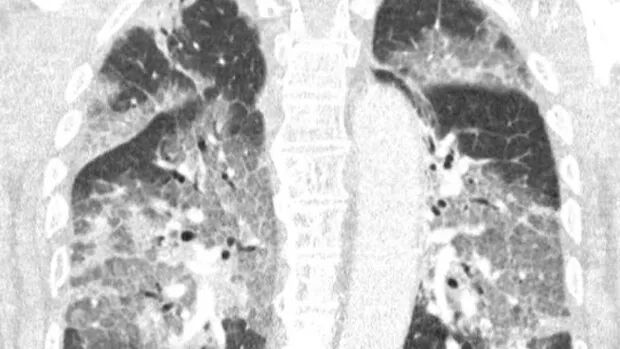

他们在信中强调了拒绝接种阿斯利康疫苗的患者现在正因为感染了病毒而不得不在重症监护室挣扎。他们详细说明他如何为生命而抗争:“我们听到了他声音中深深的遗憾和他眼睛中的绝望,这种病毒袭击了他,然而原本这一切是可以预防的。如果您允许,我们可以分享您他的肺部扫描,您不必是肺部专家就可以看到情况的糟糕,也不必是流行病学家就可以明白未接种疫苗的巨大风险。”